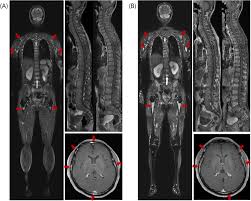

The Use Of Whole Body Mri In Multiple Myeloma Rcp Journals

The Use Of Whole Body Mri In Multiple Myeloma Rcp Journals from www.rcpjournals.org